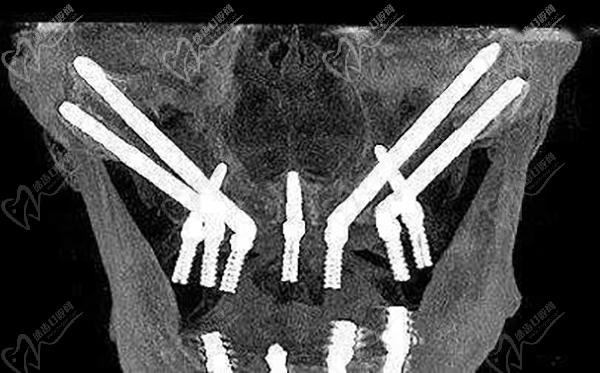

全口种植牙穿颧种植

即使是全口无牙颌种植牙,上下牙颌多颗牙齿缺失、烤瓷牙坏掉、高龄疑难无骨种植牙等等,都是可以通过先进的种植牙技术来解决的。

综上,上下牙掉了10颗是做种植牙更好的。需要到正规口腔医院进行详细的检查,确认剩下的牙齿是否坚固稳定,是否需要拔除,医生会根据患者的实际情况制定更加合理的种牙方案。采用先进的all-on-4、all-on-6即刻负重微创种植技术,仅需要4-6颗植体就能修复好半口牙,更能当天种牙当天戴牙冠,相当舒适便捷!

穿颧种植恢复半口牙